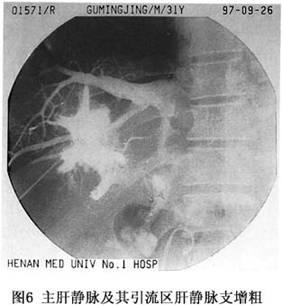

6.8.2.2 (2)經皮肝穿肝靜脈造影(percutaneous transhepatic hepatovenography,PTHV)

肝靜脈造影對B-CS應是最直接、最清晰的檢查方法。但當肝靜脈閉塞時,傳統的經股靜脈插管至下腔靜脈,再經肝靜脈開口逆行插管造影難以實施。而經皮肝穿肝靜脈造影,不僅簡便、安全、且成功率高,多數情況下,在肝靜脈顯影的同時,下腔靜脈亦可同時顯影(圖5)。鄭州大學一附院將下腔靜脈造影及經皮肝穿肝靜脈造影作爲診斷B-CS的常規檢查項目,除早年的部分病例外,497例手術的病人做了檢查,29例造影劑進入包膜下或膈下,468例造影成功,從而對B-CS最終確立了診斷,並明確了分型。近年來的353例,均在電視屏幕明視下造影,成功率達100%。

正常肝靜脈造影應爲棒狀或伴有部分分支顯影,造影劑經下腔靜脈流入右心房。當肝靜脈出口部受阻時,可見主肝靜脈及其引流區域的肝靜脈支增粗(圖6)。慢性病例,可見肝內形成側支循環,出現“蛛網徵”(cobweb’sign,圖7),如若下腔靜脈病變隔膜位於主肝靜脈出口部以上,且肝靜脈本身未被累及時,可見主肝靜脈擴張,下腔靜脈亦擴張(圖4)。在急性病例,肝靜脈可有狹窄、階段性阻塞,在肝內可見側支循環形成或與門靜脈分支形成短路,此時門靜脈干支亦可顯影。少數急性或亞急性病例,除肝靜脈廣泛狹窄外,其出口部阻塞或呈沙漏狀,此與肝小靜脈阻塞病(venoocclusive disease of the liver,VOD)相當難以鑑別。當主幹靜脈完全受阻時,造影劑經肝內的側支循環,再由肝短或肝背靜脈在第三肝門部流入下腔靜脈,這些靜脈數目不一,有時很粗大,特別是肝右後下靜脈,直徑有時可達2.0cm(圖8)。值得強調指出的是不少B-CS病例(如Ⅱ型和Ⅲb型),主肝靜脈出口部閉塞,經下腔靜脈插管做逆行肝靜脈造影,是難以實施的,對這種病例,經皮肝穿肝靜脈造影對B-CS的診斷,更有決定性的意義。